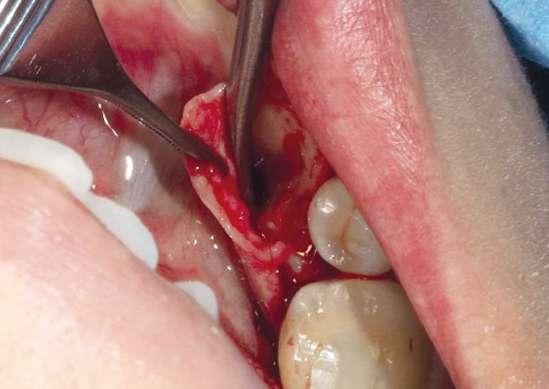

Tal y como se puede observar en las imágenes (Fig. 3 y 4) se realizó una incisión sulcular siguiendo el surco gingivodentario lingual sin descargas para despegar un colgajo a espesor total que facilitó un campo quirúrgico suficiente como para poder realizar la ostectomía hasta descubrir la corona del diente (Fig. 5).

La ostectomía se realizó de manera cuidadosa, tanto con el colgajo y las estructuras del suelo de boca, como con los dientes adyacentes y sus raíces. En este caso el diente no requirió odontosección, por lo que su exodoncia pudo ser completada usando un botador recto y unas pinzas adson para su retirada del alveolo (Fig. 6).

Figuras 1 y 2. Situación inicial y anestesia. Figuras 3 y 4. Incisión y despegamiento del colgajo lingual festoneado.

Figuras 5 y 6. Ostectomía y exodoncia con botador tipo elevador recto.